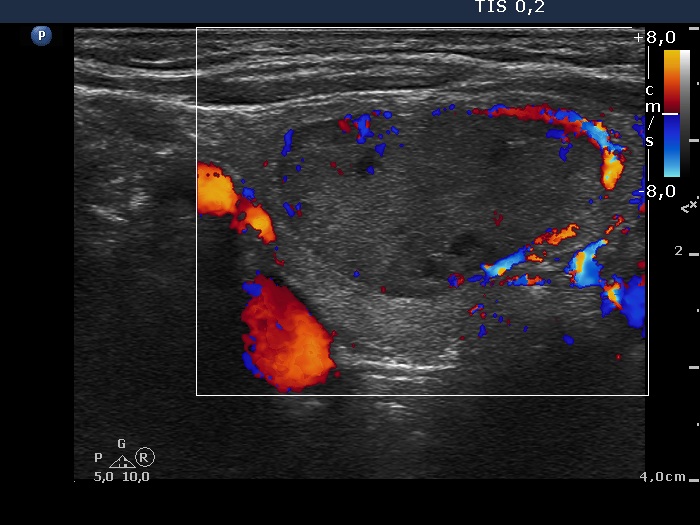

Ultrasonography. The thyroid was minimally hypoechogenic. There was a discrete lesion in the upper part of the right lobe. It was equivocal whether this echo abnormality was a nodule or not. A relatively large hypoechogenic, inhomogeneous nodule was in the lower half of the right lobe. This nodule did not present halo sign, but did a perinodular blood flow.